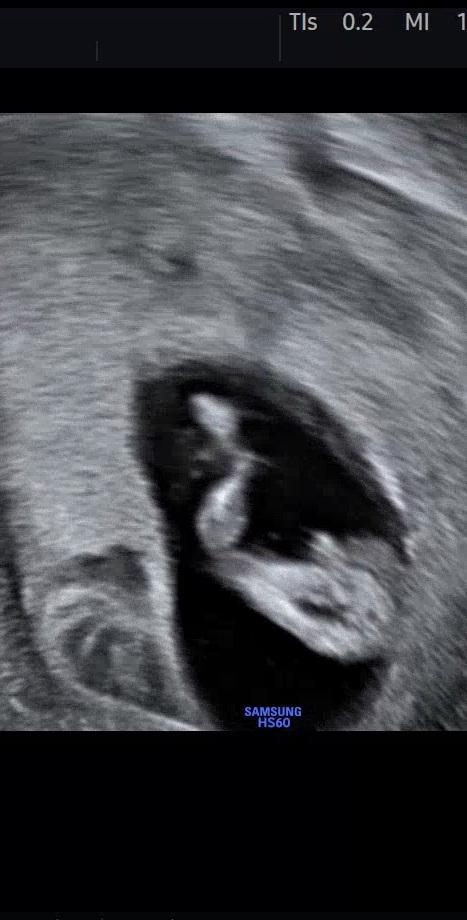

์์ฐ ๋ฑ ๋ณด์ด๊ธดํ๋๋ฐ ์ด๋ ๊ฒ ์ ๋ช ํ๋ฐ๋ ๋ธ๋ก ๋ฐ์ ๋๋๋ผ๊ท์ 11์ฃผ๋ฉด ์ข ๊ธฐ๋ค๋ฆฌ์ ์ผํญ๊ฑฐ๊ฐ์์!!

11์ฃผ5์ผ ์ฑ๋ณ ๐ถ์ธ๊ฐ? ์๋ ค์ฃผ์ธ์ฉ!

์ ์๋์ ์๋ค์ด์ด๋ ๋ธ์ฒ๋ผ ๋ณด์ผ ์ ์๋ค๊ณ ํ์ จ๋๋ฐ ๋ธ์ผ๊น์? ์๋ค์ผ๊น์ฉ?